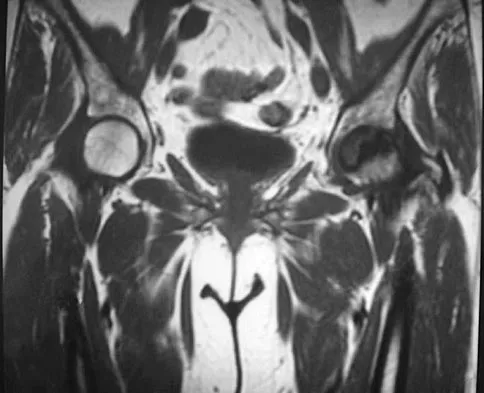

A 2-year-old child has been referred for management of congenital kyphosis. Neurologic examination is normal, and radiographs show a type I congenital kyphosis. Which of the following anomalies is seen in the MRI scan shown in Figure 6?

Explanation

There is a high incidence of intraspinal anomalies in patients with congenital scoliosis and kyphosis. Bradford and associates reported an incidence rate of 38% in 42 patients. The MRI scan shows that the filum terminale is thickened and adherent distally in the spinal canal. Although the conus is at L1, which may be normal, neurologic dysfunction may occur with further growth. There are no signals of high intensity within the cord that would suggest a syrinx. A Chiari II malformation would be found in the upper cervical region, not shown in this MRI scan. Meningocele and diastematomyelia are not present. Bradford DS, Heithoff KB, Cohen M: Intraspinal abnormalities and congenital spine deformities: A radiographic and MRI study. J Pediatr Orthop 1991;11:36-41.

- Mimaston MJ: Occult intraspinal anomalies and congenital scoliosis. J Bone Joint Surg Am 1984;66:588-601.